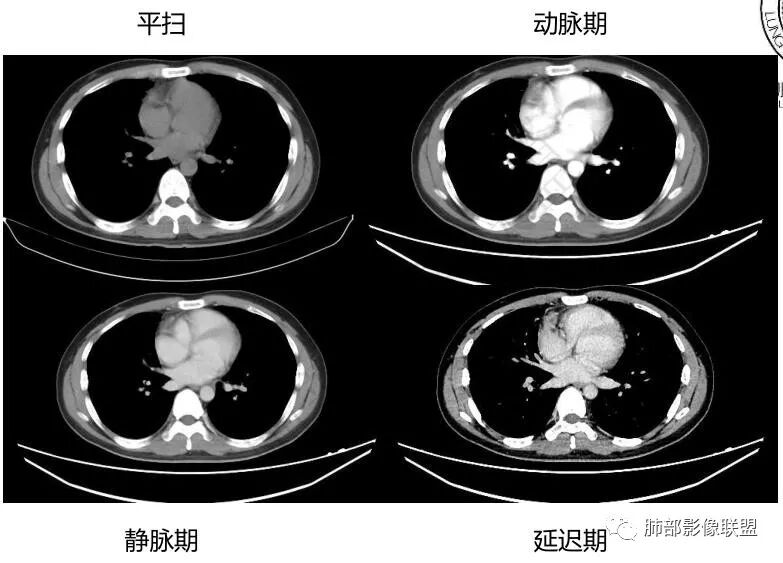

中青年男性,前纵膈偏右侧软组织肿块,形态不规则,有分叶,密度均匀,增强病灶轻中度强化,内部可见低或无强化区域,病灶与血管周围间隙分界不清晰,考虑恶性或交界性肿瘤,胸腺类癌>生殖细胞瘤>淋巴瘤。

青年男性,前上纵隔占位,渐进强化,坏死不明显,nse稍高,首先考虑类癌,鉴别精原,内胚窦瘤,需要结合实验室检查HCG,AFP等

中年男性,胸痛,既往健康,前上纵隔软组织肿块,形态不规则,密度不均,没有血管包埋及受侵征象,呈不均匀强化,考虑胸腺瘤,鉴别淋巴瘤,精原细胞瘤,胸腺癌

前纵隔右侧见大肿块,边缘清,同侧内乳动脉增粗,渐进性延迟强化明显,强化密度不均匀,中心见偏低密度灶,上腔静脉内后侧推压移位(提示肿块质地偏硬),副神经节瘤,与巨淋巴细胞增生症鉴别。

青年男性,咳嗽,右上前纵隔不规则肿块,分叶,上腔静脉受压,内乳动脉增粗,延迟强化明显,坏死不明显,考虑来源纵隔,胸腺瘤,淋巴瘤,神经源性肿瘤都可以,比较年轻,猜个淋巴瘤吧。神经源性肿瘤代排。

青年男性,前纵隔软组织肿块,偏右侧生长,边缘多发分叶,包绕临近血管生长,增强后轻度强化,并呈渐进性,可见点状坏死,考虑胸腺瘤,鉴别淋巴瘤,生殖细胞肿瘤,巨淋巴结增生症

青年男性,前纵隔偏右侧软组织肿块,密度均匀,分叶,渐进性不均匀强化,可见点状坏死,考虑胸腺瘤,鉴别生殖细胞肿瘤,淋巴瘤,CD。

青年男性,前纵隔偏右侧肿块,分叶,与邻近血管分界不清,上腔静脉受压,不均匀渐进强化,点状坏死,考虑胸腺瘤,鉴别胸腺类癌

男性32岁前纵隔偏右侧见一不规则软组织影,边缘毛刺,呈分叶征,同侧内乳动脉增粗,延迟性强化,内见条状分隔影,考虑胸腺瘤(B1、2,临界年龄段,分隔有些提示倾向),NSE轻度升高,中度强化,类癌代排。内胚窦及精原等生殖细胞肿瘤影像不符合,建议结合实验室检查

年轻男性,NSE稍高,前纵隔偏右侧不规则实性肿块,平扫密度均匀,增强渐进性不均匀强化,内见低密度区,似见条样分隔。考虑为胸腺瘤,建议实验室检查HCG,AFP等鉴别生殖细胞肿瘤

青年男性,前上纵隔占位,偏侧生长,边缘不规则,可见分叶及分隔,内见少量无强化低密度区,常规考虑胸腺瘤,NSE稍偏高一点,会不会是实验室误差?

前纵隔右侧不规则软组织肿块,边缘欠清,增强渐进性强化,内见星状无强化分隔,部分分隔延迟强化,青年男性,首先考虑精原细胞瘤,鉴别胸腺瘤,NSE轻度升高,类癌也需鉴别!

前纵隔肿块,轻度分叶,边界不清楚,延迟强化,可见分隔,倾向恶性或具有一定侵袭性病灶。